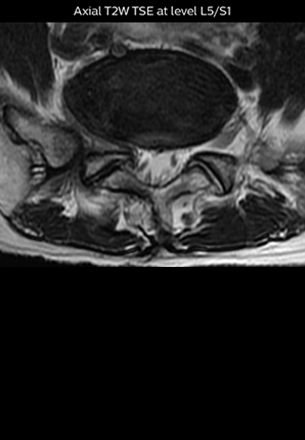

“The intra-luminal signal of veins, especially around the intervertebral space, can be suppressed well with NerveVIEW. As a result, we can easily observe the detailed nerve structure around the posterior ganglion,” he says. “This is why we use 3D NerveVIEW for intraforaminal stenosis and extraforaminal stenosis/herniation (lateral disc herniation). On the other hand, if herniation is suspected to exist inside the dorsal root ganglion (DRG), balanced TFE or ProSet-FFE is applied. NerveVIEW is not suitable for evaluating the median type of herniation.” The SE-EPI DWI-based method for MR neurography works well for large FOV exams like whole-body MRI, but focal examination of nerves is often limited by the attainable spatial resolution (both inplane and slice direction) and geometric distortion. “3D NerveVIEW achieves higher in-plane resolution – close to our other routine spine sequences – and the source images can be used instead of adding a fat-suppressed T2-weighted sequence,” Tanji says.

According to Tanji, methods such as ProSet FFE, STIR or 3D VISTA are anatomically nonselective because background signals, for instance from blood vessels, often interfere with nerves, which hampers evaluation of details, especially at the peripheral side of the nerves.